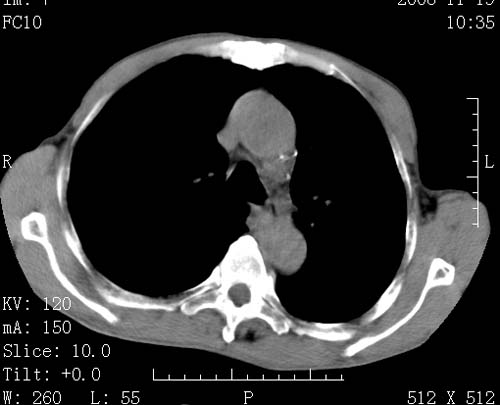

标题: CT16691:m 67 胃镜确诊食管下段及贲门癌 [打印本页]

标题: CT16691:m 67 胃镜确诊食管下段及贲门癌

术前查体,双肺部结节是转移?结核?请点评

1)符合食管癌表现。2)两肺及纵隔淋巴结多发性转移瘤。3)左肺上叶舌段及两肺下叶炎症感染。

1)符合食管癌表现。2)两肺及纵隔淋巴结多发性转移瘤。3)左肺上叶舌段支气管扩张伴感染.

食管癌伴双肺转移,评述:肺部毛细血管网丰富,全身血液均快速流经肺部,癌细胞容易过滤定植,形成转移瘤,影象特点为以毛细血管末梢为中心的结节灶,边缘光滑锐利,少见有中心空洞着,不同来源的转移瘤可有各自特点,如甲状腺癌为双肺弥漫性微结节,本例有原发灶,双肺影象灶典型,左肺舌段条带状网格样伴胸膜天幕征,可视为癌性淋巴管炎。

左肺舌段有斑点钙化灶,能否说明是结核而不是转移?如果是转移将放弃手术改成化疗,如果是结核将考虑择期手术